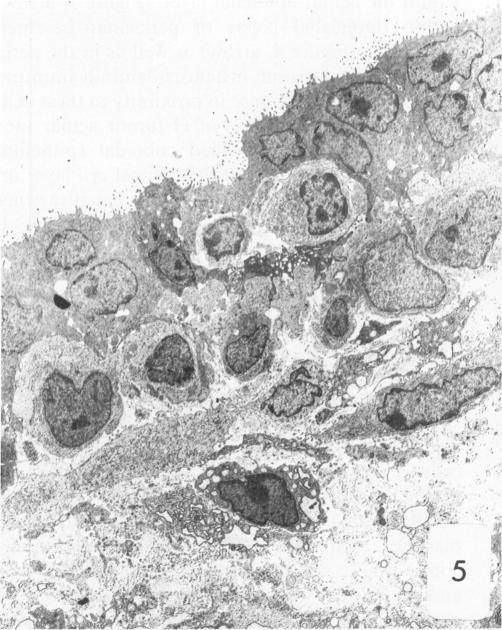

Dunning R3327-H rat prostate adenocarcinoma cells, when grown in syngeneic (Copenhagen) rats or nude mice, produce tumors with prominent hypercellular stroma. The authors have previously demonstrated the presence of anomalous steroid-sensitive cells in both the epithelium and stromal compartments of this model system. In order to better understand the histogenesis of these cells, the authors studied samples of the tumor which were radiolabeled overnight with tritiated dihydrotestosterone (3H-DHT). Frozen sections of the tissues were thaw-mounted onto autoradiographic emulsion-coated slides to permit silver grain identification in association with nuclei of androgen-sensitive cells. Surprisingly, numerous silver grains were found to be associated with nuclei of large cells within the stroma. Therefore, these cells were termed "epithelioid" pending confirmation of their origin. To further define these cells and their relationship to the surrounding matrix, autoradiograms have now been examined immunohistochemically with antibodies directed against the basement membrane glycoprotein, laminin, as well as antibodies specific for intermediate cytoskeletal filaments. Following identification of acinar basement membranes, epithelioid cells were identifiable both in the stroma and in the acinar epithelial cell layer. Histochemical staining with acid phosphatase, a marker for prostatic epithelium, was performed and shown to be present in acinar epithelial cells as well as in epithelioid cells. Additionally, fluorescence-activated cell sorting was employed to characterize the DNA content of cell types within the H tumor. Epithelioid cells were found to be in highest concentration in an aneuploid peak with a ploidy of approximately 6N. The autoradiographic, immunohistochemical, cytometric, and ultramicroscopic studies suggest that 1) epithelioid cells are epithelial derived stromal cells; 2) these epithelioid cells arise by pathologic division of aneuploid neoplastic precursor cells of approximately 3N ploidy, which are found within the prostatic epithelium; and 3) the resulting 6N cells degrade the basement membrane locally, invade the stroma, and populate it. Here, they can be distinguished from fibroblasts by their size, acid phosphatase activity, and hormone receptor content. Thus, the term "epithelioid" is inappropriate; and these cells should be regarded simply as large neoplastic epithelial (LNE) cells. The presence of this cell type suggests that this tumor subline represents a useful naturally occurring model for the study of the initial stages of neoplastic transformation.

邓宁R3327 - H大鼠前列腺腺癌细胞在同基因(哥本哈根)大鼠或裸鼠体内生长时,会产生具有显著细胞增多性基质的肿瘤。作者此前已证明在该模型系统的上皮和基质区室中均存在异常的类固醇敏感细胞。为了更好地理解这些细胞的组织发生,作者研究了用氚化双氢睾酮(3H - DHT)过夜进行放射性标记的肿瘤样本。将组织的冰冻切片解冻后贴在涂有放射自显影乳剂的载玻片上,以便确定与雄激素敏感细胞核相关的银颗粒。令人惊讶的是,发现大量银颗粒与基质内大细胞的核相关。因此,在确认其起源之前,这些细胞被称为“上皮样细胞”。为了进一步定义这些细胞及其与周围基质的关系,现在已用针对基底膜糖蛋白层粘连蛋白的抗体以及针对中间细胞骨架丝的特异性抗体对放射自显影片进行免疫组织化学检查。在确定腺泡基底膜后,在上皮样细胞的基质和腺泡上皮细胞层中均可识别出上皮样细胞。用酸性磷酸酶进行组织化学染色,酸性磷酸酶是前列腺上皮的标志物,结果显示其存在于腺泡上皮细胞以及上皮样细胞中。此外,采用荧光激活细胞分选技术来表征H肿瘤内细胞类型的DNA含量。发现上皮样细胞在非整倍体峰中浓度最高,其倍性约为6N。放射自显影、免疫组织化学、细胞计量学和超微结构研究表明:1)上皮样细胞是上皮来源的基质细胞;2)这些上皮样细胞由前列腺上皮内约3N倍性的非整倍体肿瘤前体细胞的病理性分裂产生;3)产生的6N细胞局部降解基底膜,侵入基质并在其中聚集。在这里,它们可以通过大小、酸性磷酸酶活性和激素受体含量与成纤维细胞区分开来。因此,“上皮样”这个术语并不恰当;这些细胞应简单地视为大肿瘤上皮(LNE)细胞。这种细胞类型的存在表明该肿瘤亚系是研究肿瘤转化初始阶段的一个有用的自然发生模型。